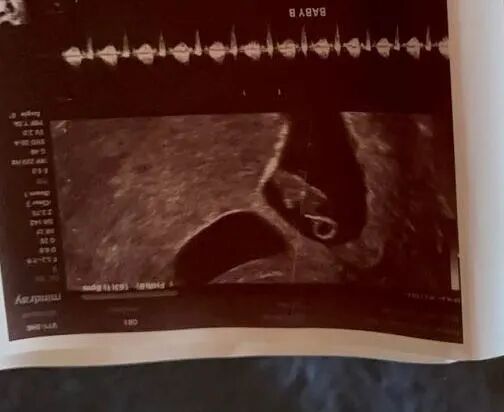

还记得那位来自加州的甜美可爱的爱妈J吗?她前不久验孕成功,今天在诊所进行了首次体检,并激动地听到了宝宝的心跳声!虽然她与来自上海的准妈妈相隔千里,但这份激动和期待的心情已经跨越了地理的界限。宝宝的每一次检查,两地的妈妈们都充满了期待和喜悦,共同期盼着下一次美好的消息。